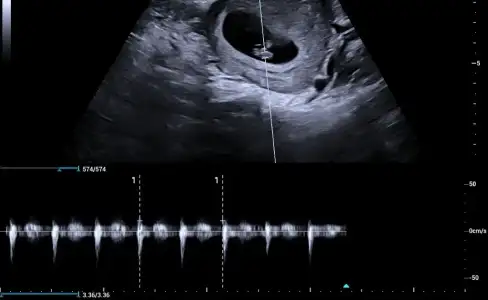

• 0ec81f3e-b806-4d93-bd0d-d864d321d9a6.webp

0ec81f3e-b806-4d93-bd0d-d864d321d9a6.webp

27,8 KB · Görüntüleme: 63

Kızlar benimkinide tahmin edin yaa kese yuvarlakmı ovalmi ben anlamıyorum burda 6+4 😂😂